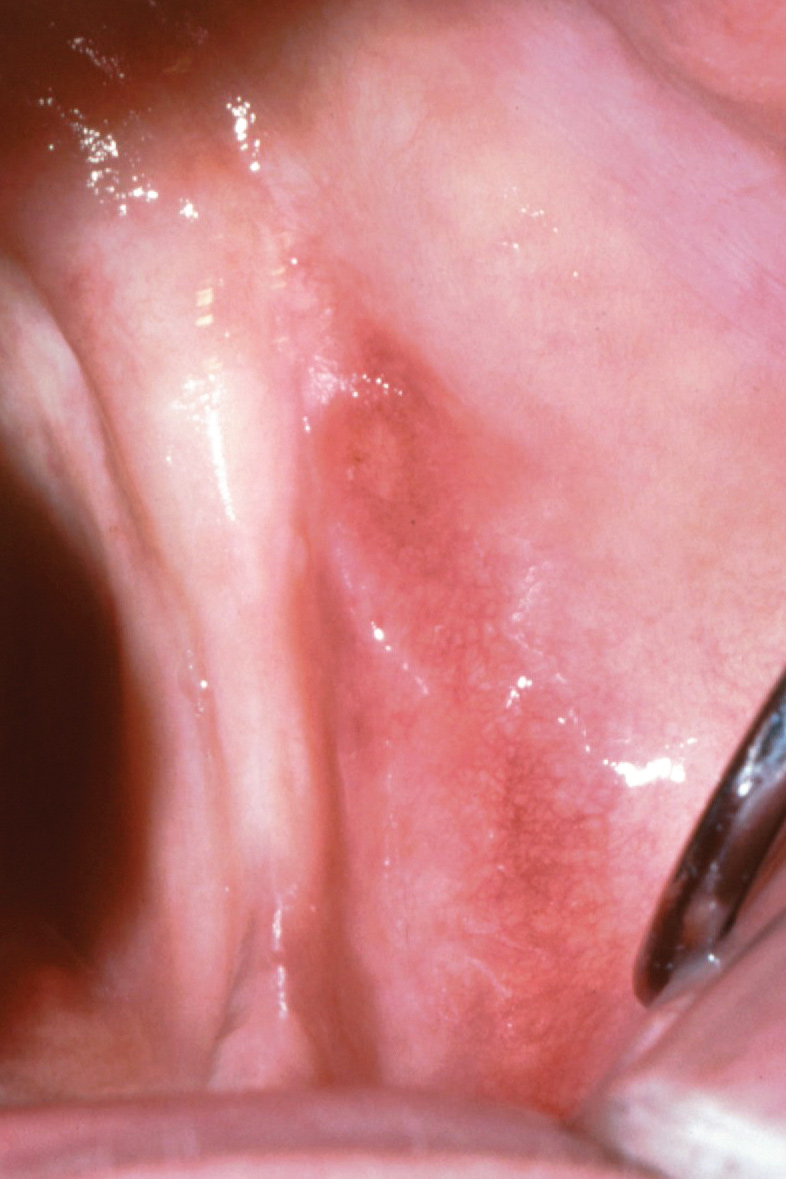

The buccal shelf presents a loosely attached mucosa,6,16 whereas the crest of the ridge usually consists of a firmly attached mucosa unless the ridge demonstrates an excessive resorptive pattern (Figure 1). The buccal shelf, meanwhile, presents a thick cortical bone and is part of the basal bone receiving tensile stimulation through the actions of muscular attachments. The anatomy and trabecular patterns also are structured to resist the forces of mastication better than the crest of ridge, although the mucosa is less keratinized and prone to displacement under pressure.5,6

Fig 1. Mandibular edentulous arch demonstrating buccal shelf lateral to ridge crest.